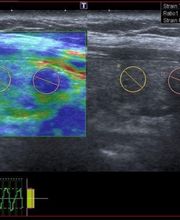

Centro Diagnostico David. Il nostro Centro è specializzato in diagnostica per immagini, vanta le tecnologie più innovative, supportate da un corredo di software di ultima generazione in grado di fornire altissime prestazioni diagnostiche in regime di low dose. Accoglienza, garbo e spiccata professionalità saranno garantite dalla nostra equipe. Tra i nostri esami potrai effettuare: Ecografia, Eco Color Doppler, Elastosonografia, Radiologia Digitale, Ortopantomografia, Teleceflometria, Cone Beam TC 3D. Prenota la tua visita contattandoci attraverso i nostri canali dedicati, utilizza WhatsApp per richiedere maggiori informazioni o compila il form contatti per ricevere delucidazioni più dettagliate.